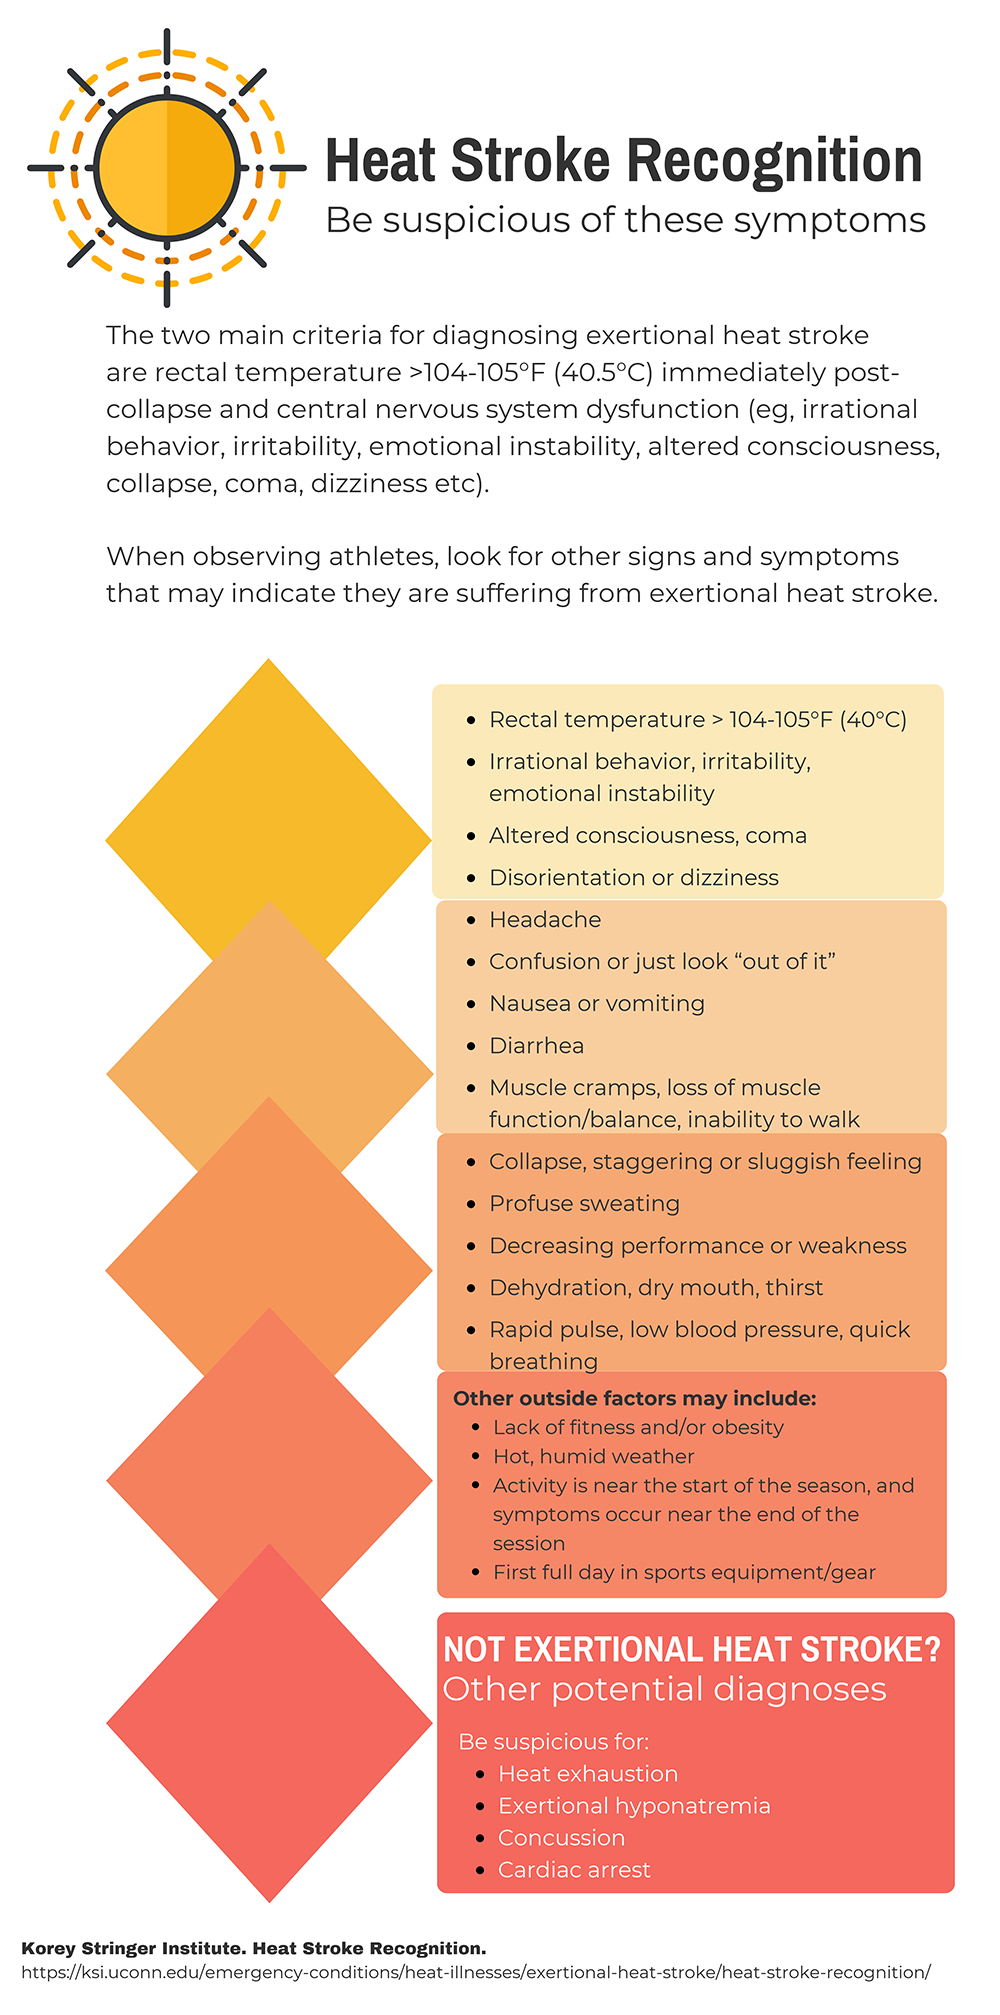

Heat stroke, whether classical or exertional, is the most serious presentation of heat-related illness. Mortality rates range from 30-80% and is universally fatal if left untreated. The diagnosis is generally clinical and defined by encephalopathy and hyperthermia > 40° C, although temperature less than 40° C should not be exclusive criteria for treatment.

The presence of mental status changes in a hot and/or humid environment should be considered heat stroke until proven otherwise. Anhidrosis is not diagnostically reliable. Ataxia is an early symptom due to sensitivity of the cerebellum; patients may also have irritability, confusion, behavior changes, combativeness, hallucinations, decorticate and decerebrate posturing, hemiplegia, and coma. Seizures are common. Neurologic injury is a function of duration of exposure and maximum temperature. The patient may be tachycardic, tachypneic, and/or hypotensive.

10. Korey Stringer Institute. Heat Stroke Recognition. Accessed September 2018.